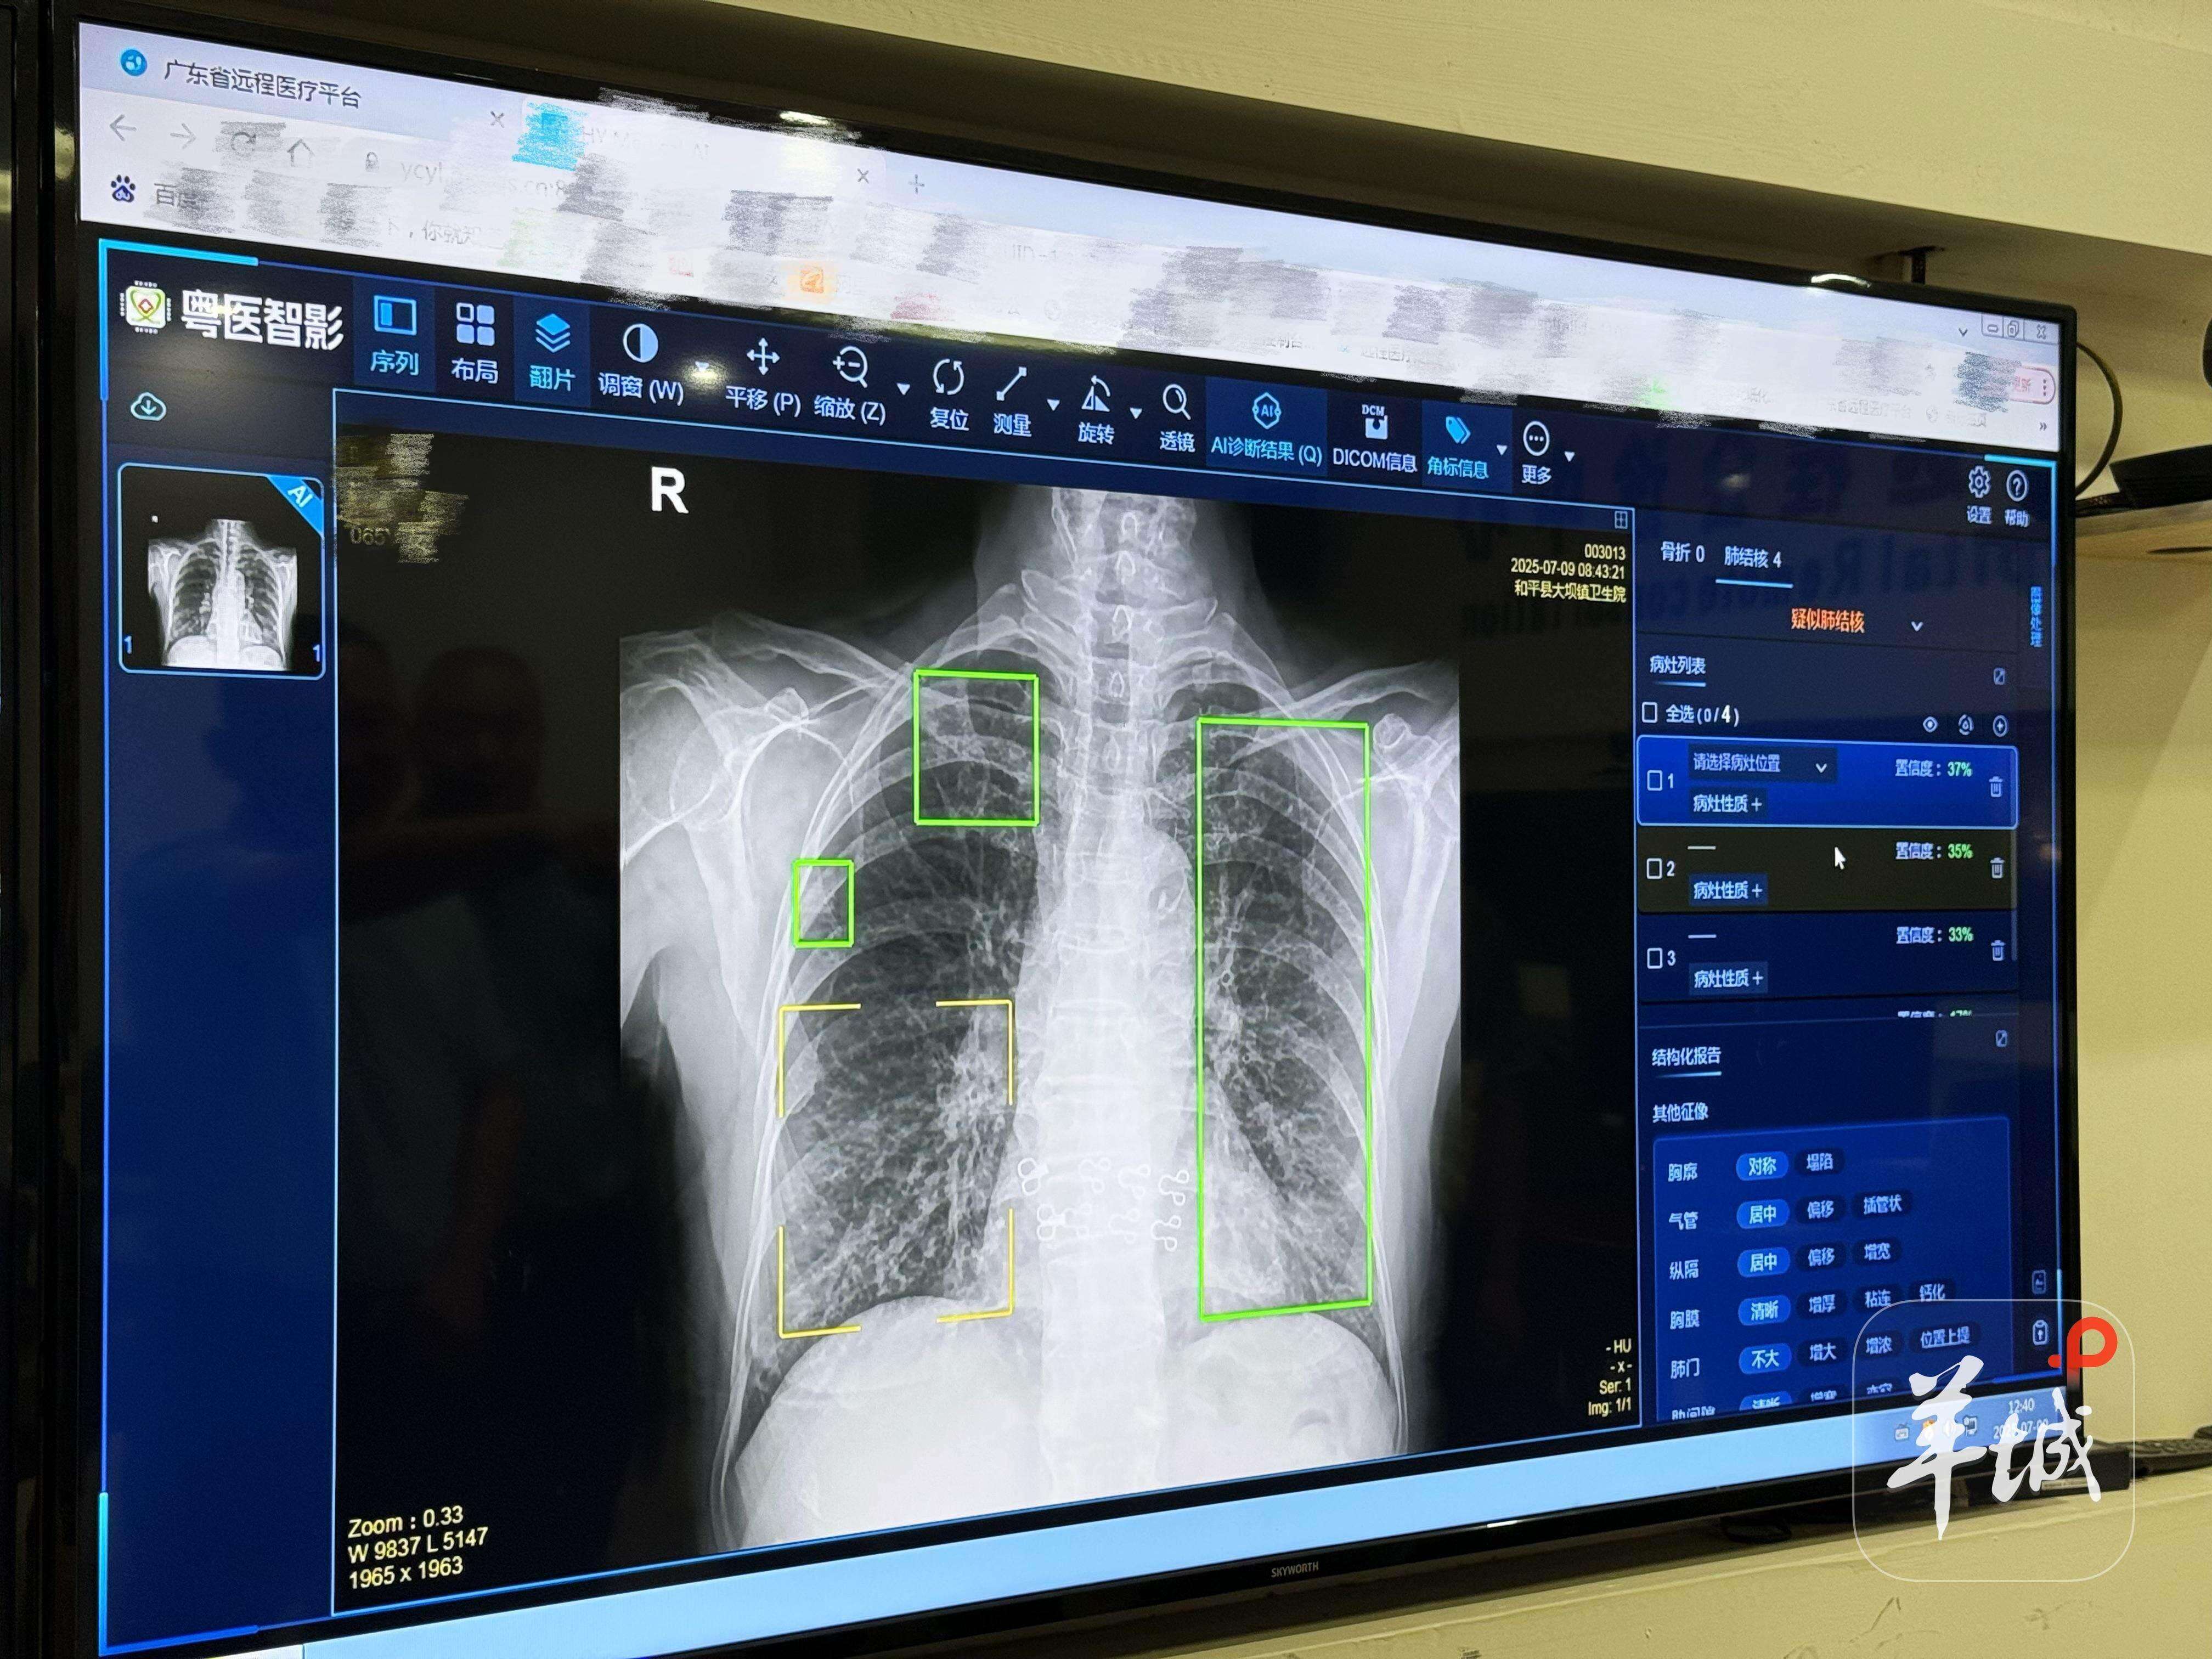

Starting July 10th, the Health Commission of Guangdong Province launched the AI-assisted medical image interpretation system known as "Yueyi Zhiying" across its telemedicine platform. The system currently supports seven types of examinations: AI-assisted diagnosis of pulmonary nodules via CT, CT-based bone density assessment, intelligent CT screening for pneumonia and rib fractures, intelligent DR screening for tuberculosis, AI-assisted diagnosis of limb fractures via DR, and CT-based coronary artery calcium scoring. All services are provided free of charge to healthcare institutions across the province.

According to reports, while traditional manual interpretation of medical images typically takes about 30 minutes, this AI system leverages powerful computational capabilities and optimization algorithms to complete analysis and generate structured reports in just 2 seconds. In terms of efficiency, the system can process the equivalent of a full day's workload of 150 human radiologists from a top-tier hospital in just one hour.

Huang Shengzhou, head of the hospital's radiology department with 30 years of experience, said, "In the past, all image interpretation had to be done manually. Now, AI acts like a second pair of eyes for doctors, supplementing image details and demonstrating greater sensitivity in detecting subtle features. This helps avoid missed or incorrect diagnoses and significantly improves our work efficiency."